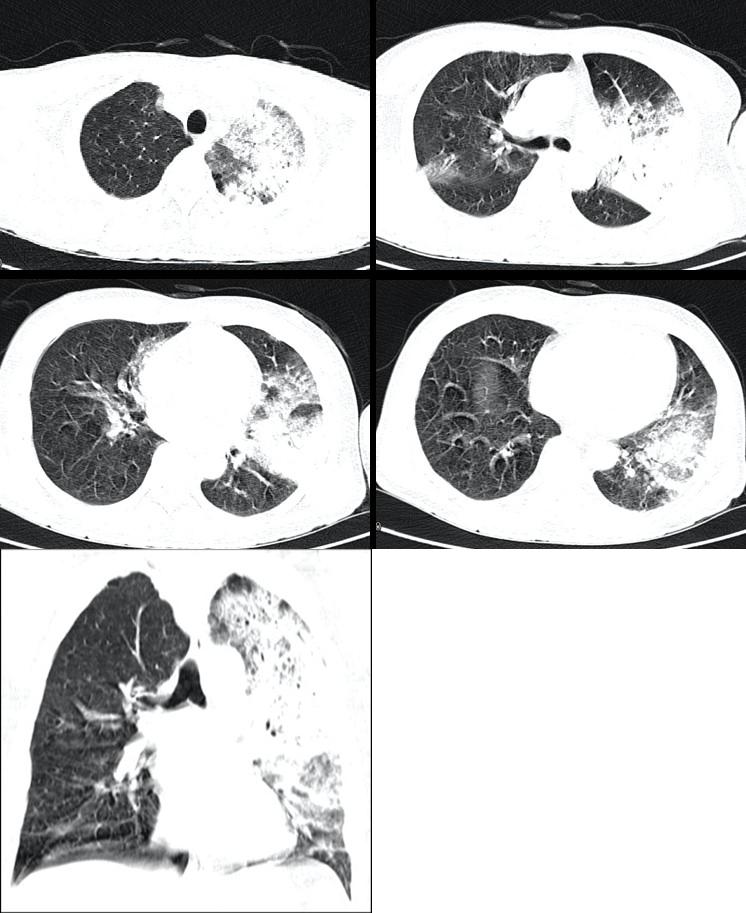

➤头颅CT未见明显异常,胸部CT如下:

军团菌肺炎的影像学特点:

➤早期通常为单侧下叶渗出;

➤迅速进展到多叶;

➤胸腔积液常见。

有日本学者研究了38例军团菌肺炎的影像学特征,归纳其CT特征为:

➤单侧/双侧的单独/多灶性实变与GGO(磨玻璃影);

➤支气管血管束周围边界清晰的实变病灶与磨玻璃样阴影混杂是军团菌最常见的CT表现之一。